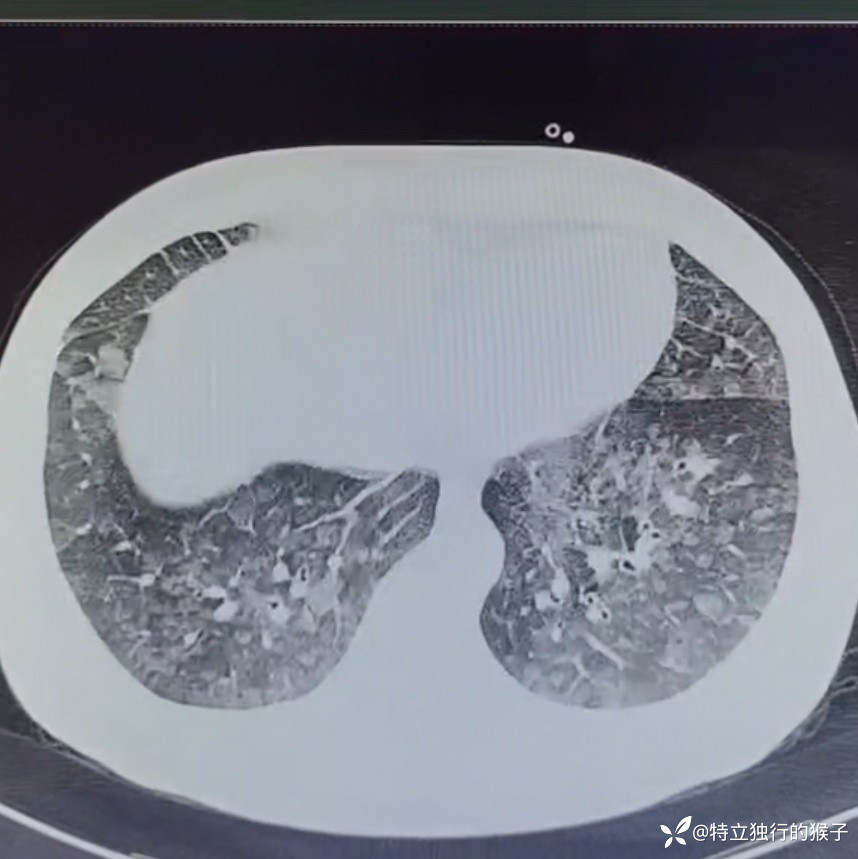

30y/M,1天前出现咳嗽,咳粉色泡沫痰,胸痛,胸闷气急,无发热。既往有肾炎病史。

查体:SpO2 85%,血压169/125mmHg,神志清,呼吸急促,口唇紫绀,两肺呼吸音粗,两肺闻及弥漫湿啰音,双下肢无水肿。

cTnI 0.66ng/ml;NT-proBNP 4183ng/ml。D-Dimer 0.17mg/l;肌酐271umol/L,BUN15mmol/L。